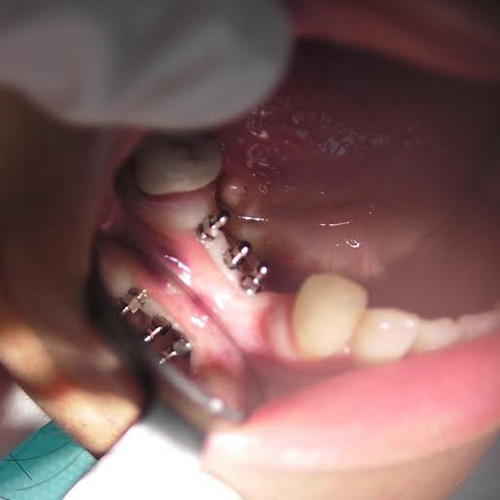

Implants: Before & After

More Pictures